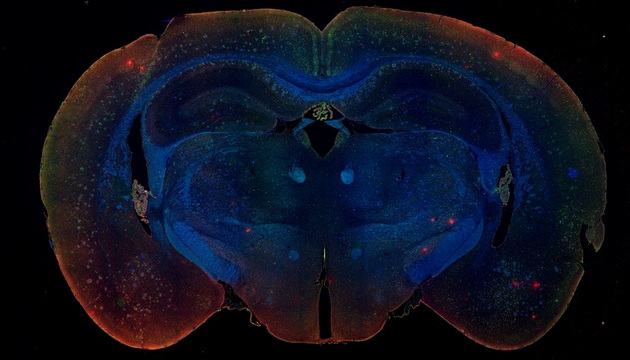

研究等常規熒光觀察需要。 ●研究級熒光觀察方案,研究級倒置熒光MF53-N和研究級正置熒光MF43-N,研究級機身,配備明美MG-120等LED熒光光源,可選配不同的熒光激發塊,半復消色差物鏡對弱信號也有良好的成像能力,滿足FISH、CTC等高要求成像。 ●熒光切片掃描方案,多重熒光數字切片掃描儀MES200,高速全景拼接,精準掃描,助力腦片研究及多重熒光標記分析,推動熒光成像技術發展。